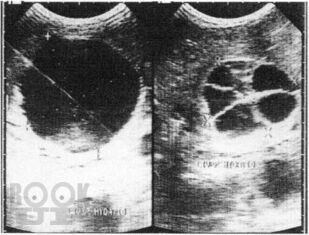

В Практическом руководстве отражены вопросы клинико-лабораторно-лучевой диагностики эхинококкоза печени с сипользованием УЗИ, РКТ, МРТ и современные аспекты лечения. Практическое руководство предназначено для специалистов лучевой, клинической, лабораторной диагностики, терапевтов, гепатологов, хирургов, онкологов.